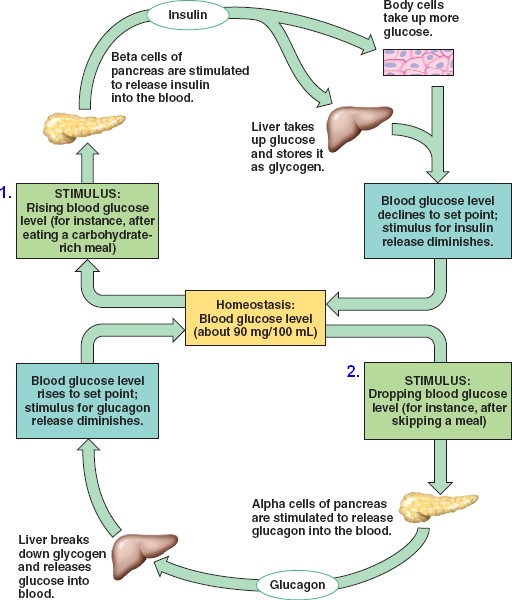

45_12GlucoseHomeostasis

homeostasis-glucose.html